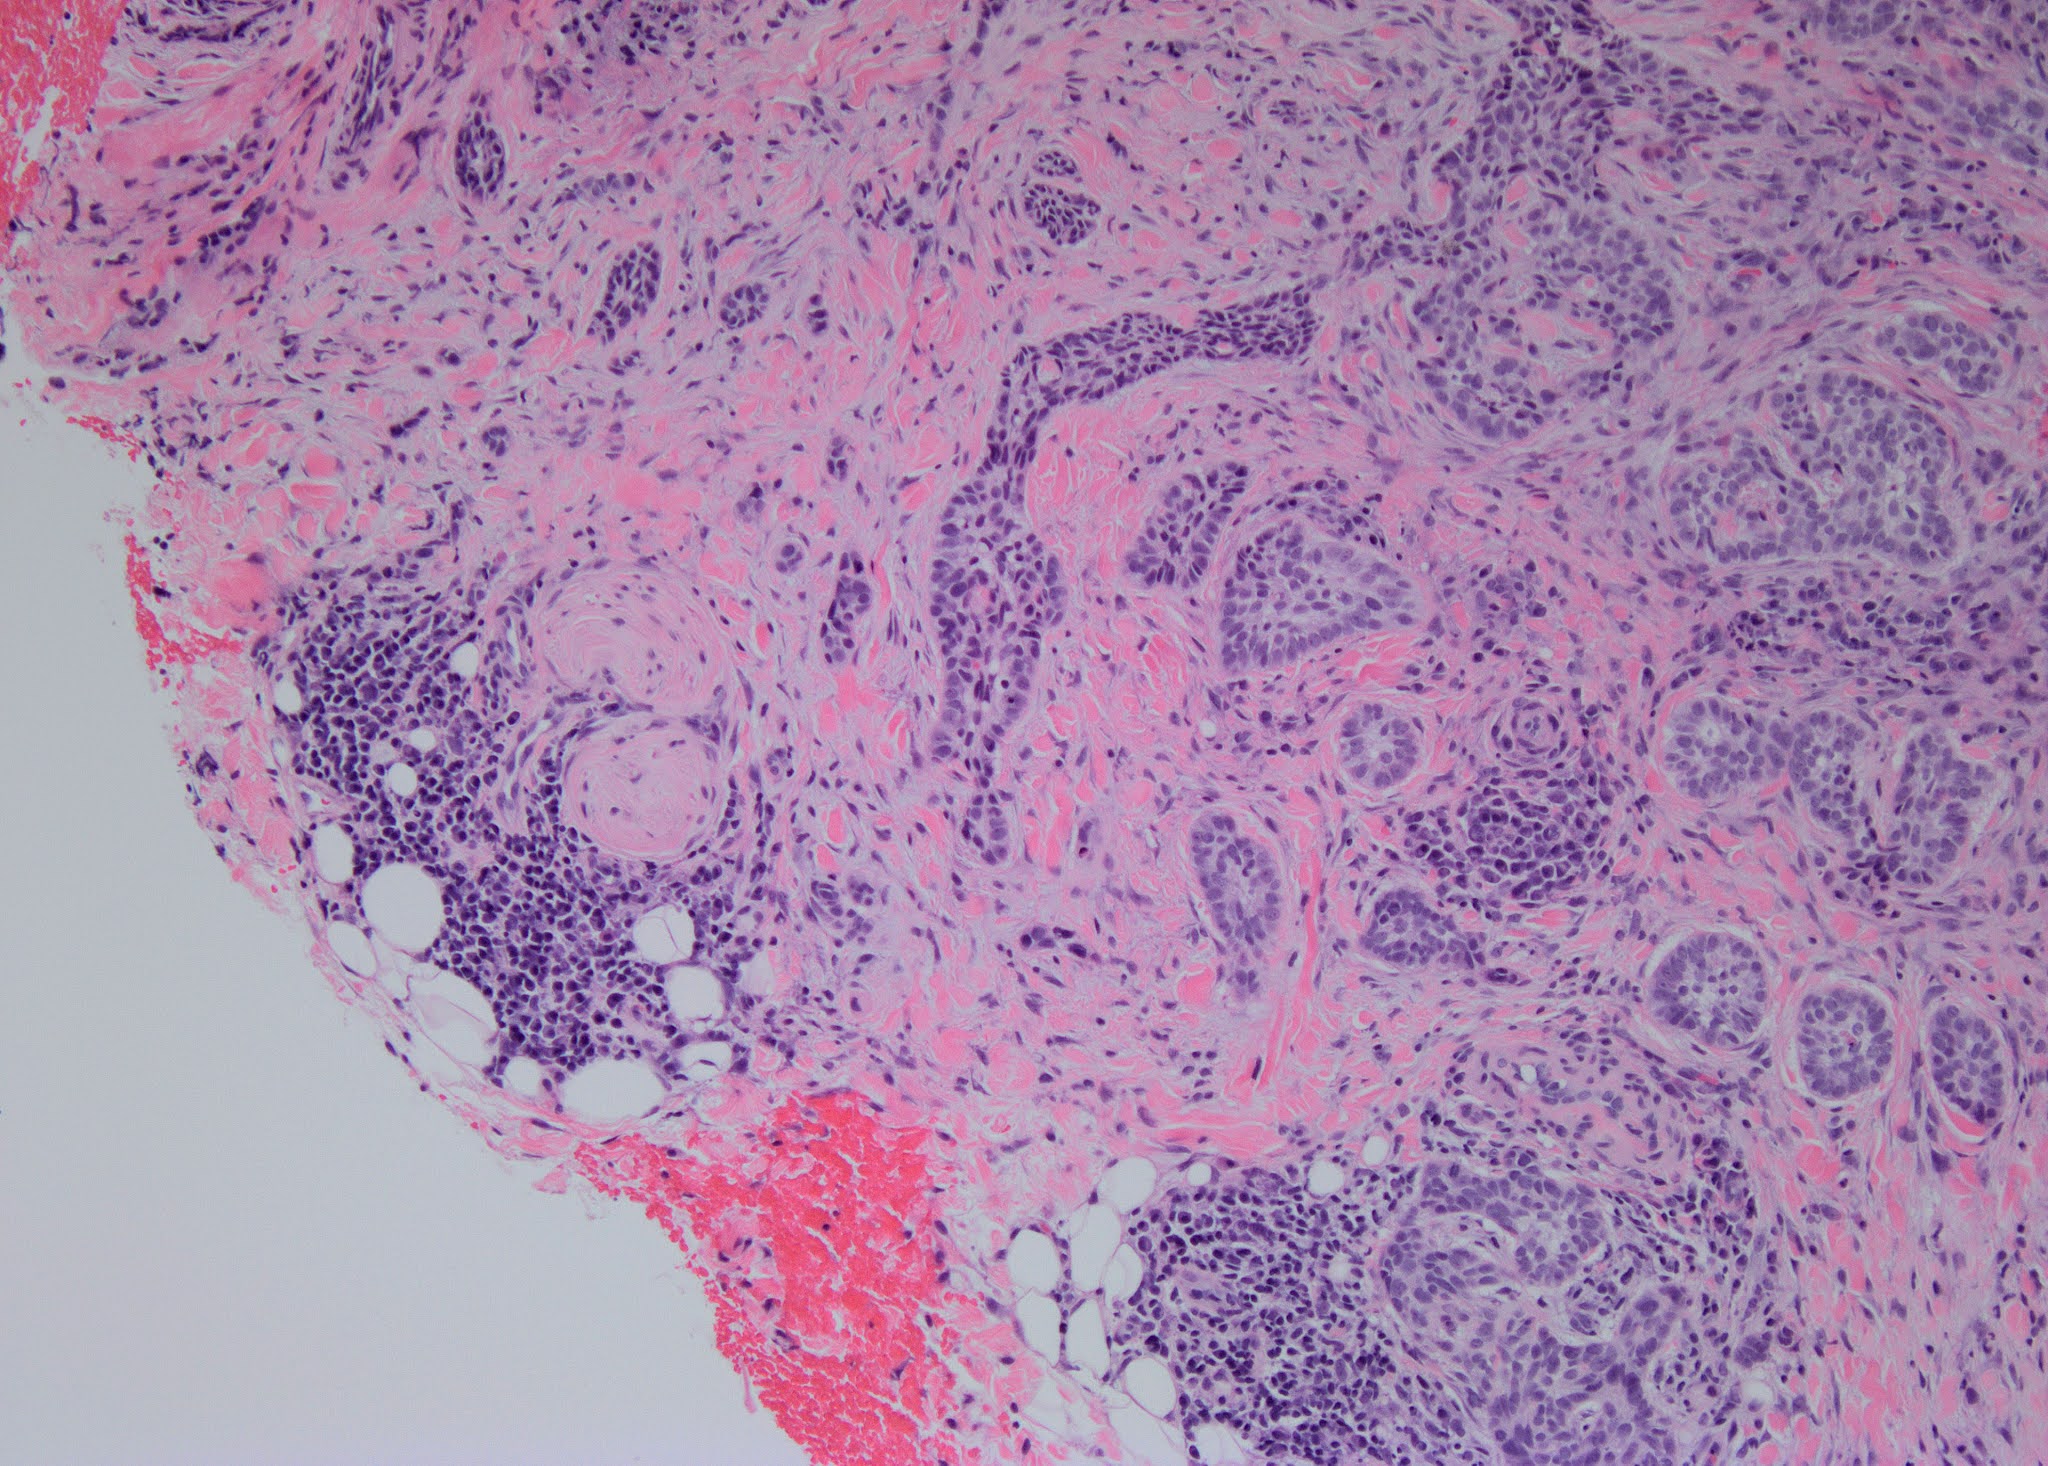

A skin biopsy was performed.

Pathology: Section shows prominent spongiosis with focal parakeratosis. The epidermis shows focal necrotic keratinocytes and intra-epidermis lymphocytes. There is zonal epidermal necrosis in the center of the biopsy, associated with hemorrhage and a perivascular lymphocytic cuffing of the superficial dermal vessels. The dermis shows mild perivascular neutrophils infiltration. There is no atypical lymphocyte or malignancy seen. The deeper dermis and subcutaneous fat are normal. Extensive lichenoid dermatosis consistent with erythema multiforme. No atypical lymphocyte seen. (Fig 3)

Fig 3